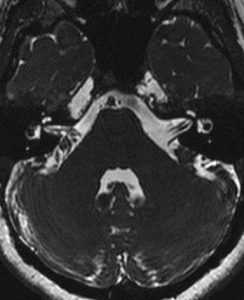

Вестибулокохлеарный нерв (VIII) состоит из 4 пучков. Опухоли происходят обычно из вестибулярной его части. Шваннома - инкапсулированная доброкачественная (градация 1) опухоль, происходящая из дифференцированных неопластических шванновских клеток оболочек периферических нервов. Невриномы ММУ составляют около 3% опухолей головного мозга. Часть шванном (двухсторонние слуховых нервов) связана с НФ 2 типа. Пик частоты между 40 и 60 годами. Растут медленно и крайне редко малигнизируются. Клинические проявления связаны с нарушением функции нерва и компрессией ствола. Шваннома может происходить из любого отрезка по ходу нерва и хорошо прослеживается при МРТ области ММУ. Невринома видна как на Т2-взвешенных, так и на Т1-взвешенных МРТ в виде округлого образования. Невриномы хорошо и равномерно усиливаются после МРТ с введением контрастного вещества. Невриномы области цистерны могут иметь компонент во внутреннем слуховом проходе, особенно, хорошо видимый при МРТ головного мозга с контрастированием. Изредка встречаются невриномы полностью расположенные внутри канальца. Они составляют наибольшую диагностическую сложность при МРТ, требуют тонких срезов и контрастирования. Менингиомы ММУ обычно типично расположены и при МРТ имеют характерную форму и типичные черты при МРТ с контрастированием. Однако редко встречаются внутриканальцевые менингиомы. При МРТ они неотличимы от неврином. Холестеатомы при МРТ имеют смешанную интенсивность сигнала, в зависимости от их содержимого. На диффузионно-взвешенных МРТ холестеатомы обычно яркие.

МРТ головного мозга. Аксиальная Т2-взвешенная МРТ. Фрагмент ММУ. Холестеатома слева.